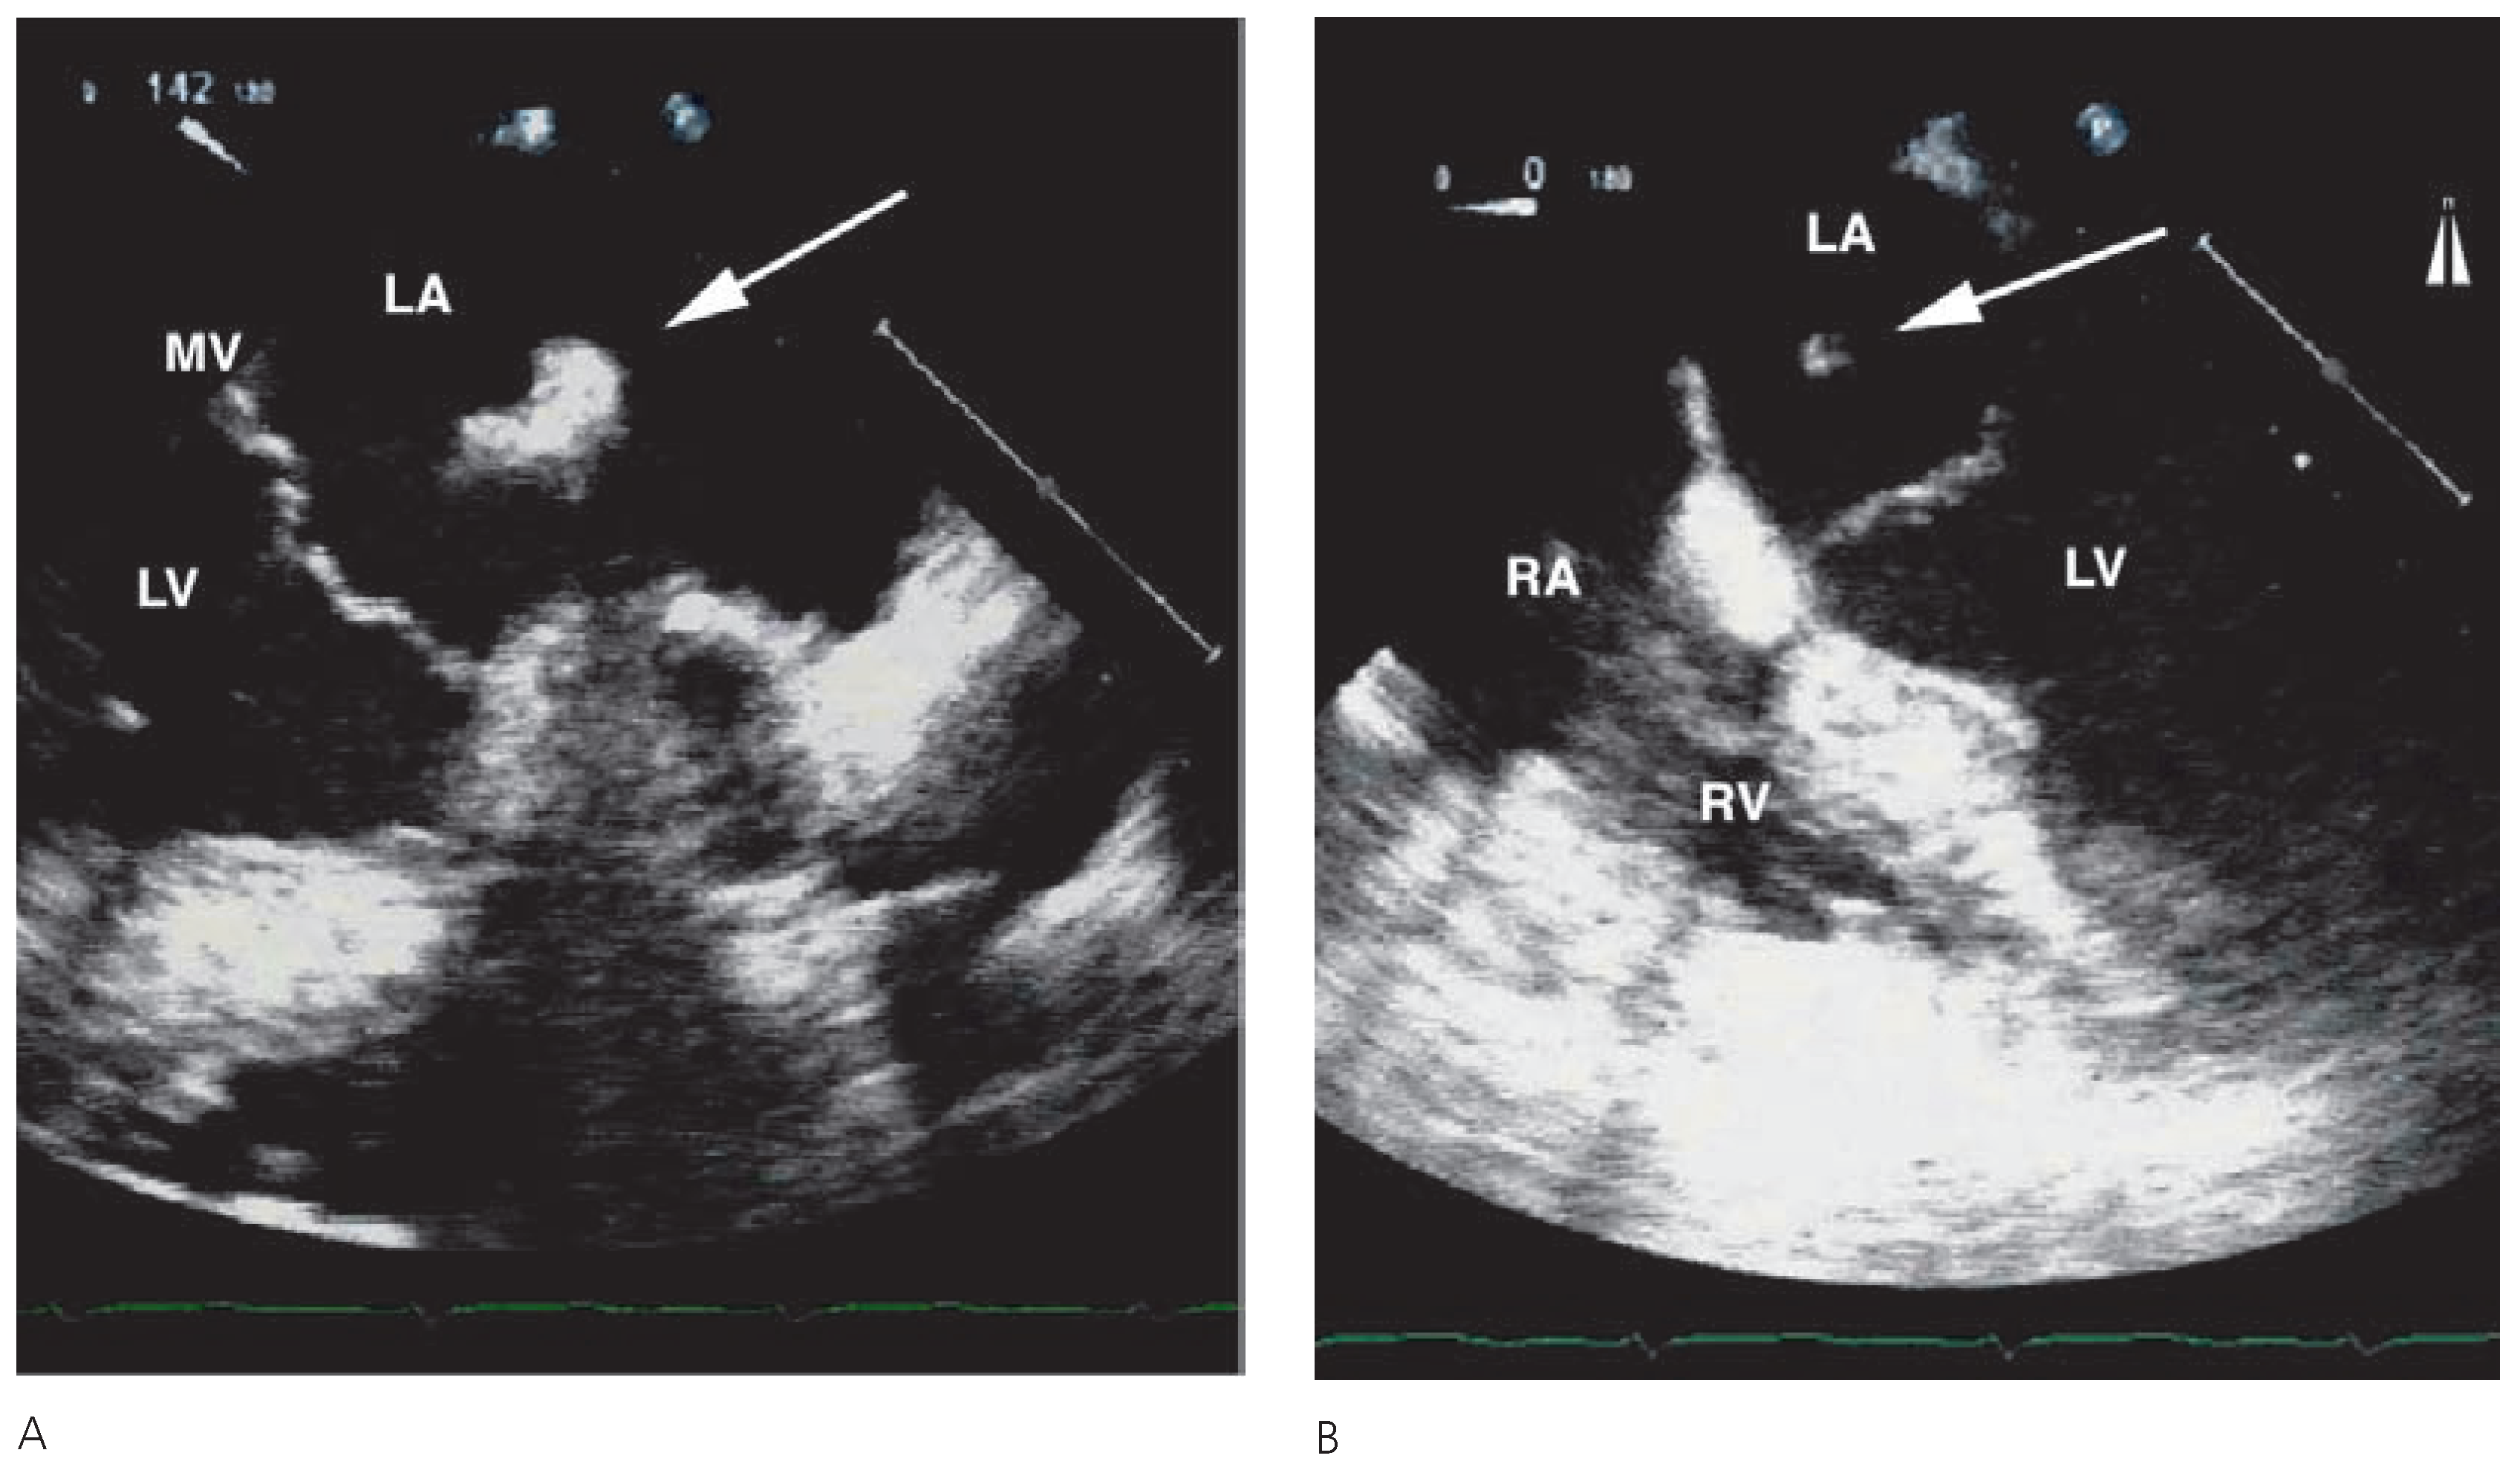

A 60-year-old male patient was referred to our hospital for coronary artery bypass graft surgery due to prior subacute myocardial infarction and subsequently angiographically diagnosed 3-vessel coronary artery disease. Preoperative transoesophageal echocardiography (TEE) revealed wall motion abnormalities, but was otherwise unremarkable. During stepwise reduction of the extracorporal circulatory assistance after uneventful course of the surgical procedure, the routinely conducted TEE revealed a well-defined homogeneous floating structure in the left atrium (Figure 1A,B). Diagnosis of a perioperative thrombus formation in the left atrium was proposed. Hence, the left atrium was incised to explore the structure leading to the diagnosis of an inverted left atrial appendage. Inversion of the left atrial appendage following cardiac surgery is a rare but important complication that can be transient showing spontaneous eversion. It can, however, result in serious complications such as necrosis with potential rupture of the left atrial wall. Therefore decision was taken towards surgical reduction of the inverted left atrial appendage. In the case of peri- or postoperative appearance of a new clearly delineated floating structure in the left atrium, an inverted left atrial appendage has to be taken into account.

Figure 1. (A) Transoesophageal crosssectional long-axis view of the heart at 142°. (B) Four-chamber-view of the heart at 0°. Arrows indicate a clearly delineated homogeneous floating structure in the left atrium. LA = left atrium; LV = left ventricle; RA = right atrium; RV = right ventricle; MV = mitral valve.